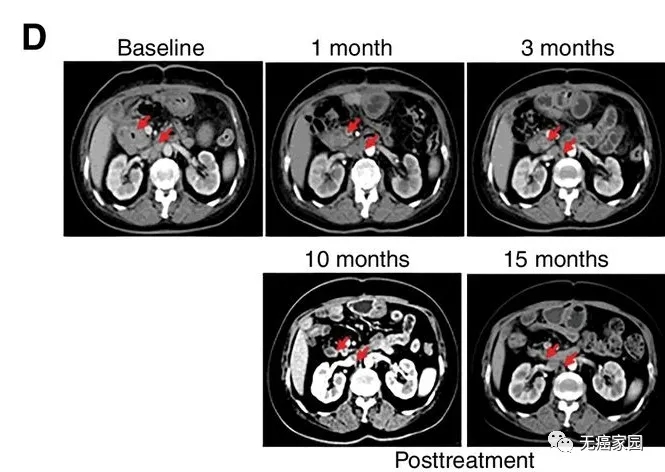

CART-RGFR细胞治疗之前和1、3、10和15个月患者1的CT扫描图像。

红色箭头表示原发肿瘤和腹膜后淋巴结转移。

研究结果显示,17例患者可评估,其中1例胆管癌患者的肿瘤完全消失,截止到目前疗效已经保持了22个月,尚未发现疾病复发。10例患者疾病稳定,疗效保持2.5~15.5个月,中位无进展生存期为4个月。